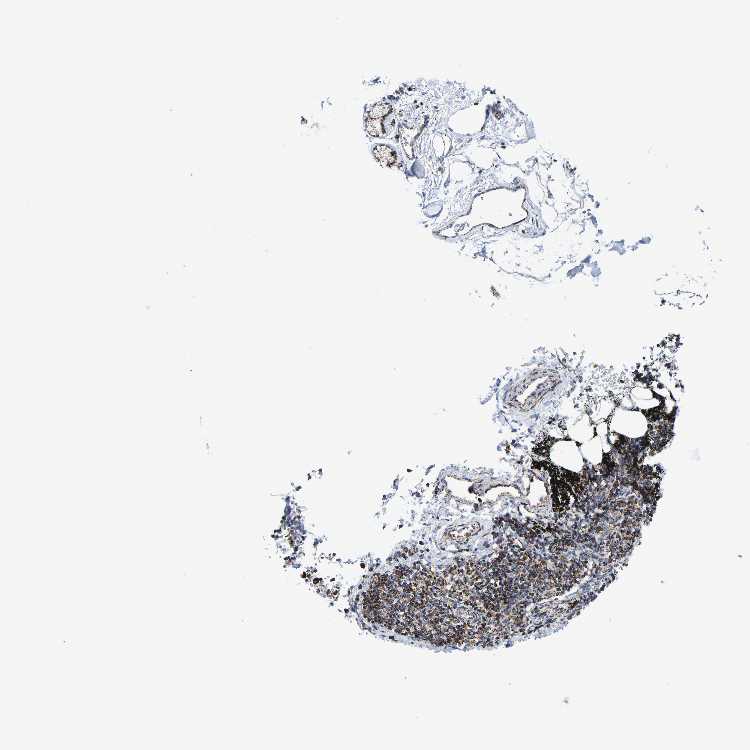

ADIPOSE TISSUE - Antibody stainingi

Antibody staining in the annotated cell types in the current human tissue is reported as not detected, low, medium, or high, based on conventional immunohistochemistry profiling in selected tissues. This score is based on the combination of the staining intensity and fraction of stained cells.

Each image is clickable and will lead to virtual microscopy that enables deeper exploration of all samples and also displays staining intensity scores, fraction scores and subcellular localization as well as patient and tissue information for each sample.

Antibody HPA022853Antibody HPA023043

Adipocytes MediumMedium